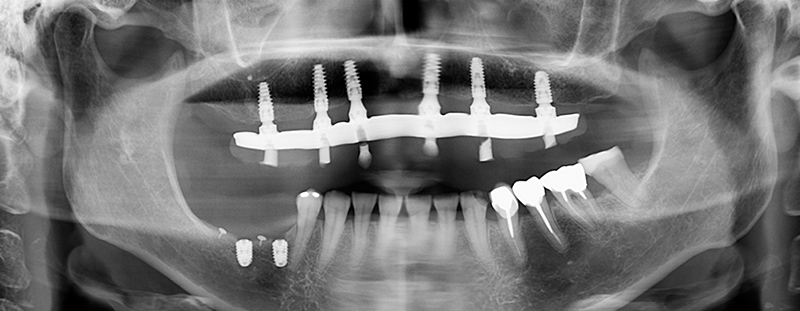

Fig. 12 : radiographie panoramique post-opératoire.

Les études ont montré les bénéfices de la chirurgie partiellement guidée par rapport à la chirurgie à main

levée en termes de précision de positionnement 3D. La trousse de chirurgie guidée INITIAL Anthogyr permet une exécution rapide de l’acte chirurgical avec peu de passages de forets à travers le guide, dans un secteur qui demande souvent un gros effort aux patients en termes d’ouverture buccale. Le foret pointeur de la trousse

permet de ne pas « glisser » latéralement dans le cas d’un angle d’attaque trop tangentiel avec la crête osseuse. Il guide le forêt pilote, afin de trouver son chemin sans contraintes.

Ce cas illustre une situation clinique courante pour les praticiens exerçant l’implantologie. Il démontre l’intérêt

d’un système avec une solution intégrée de chirurgie guidée dans la réalisation d’un cas simple.